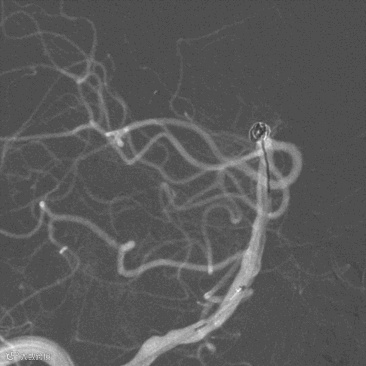

选择合适工作角度,路图下,顺Synchro14微导丝将SL-10支架微导管送至左侧大脑后动脉P2段(图6),将Echelon-10栓塞微导管送至动脉瘤瘤腔内(图7)。

图6

图7